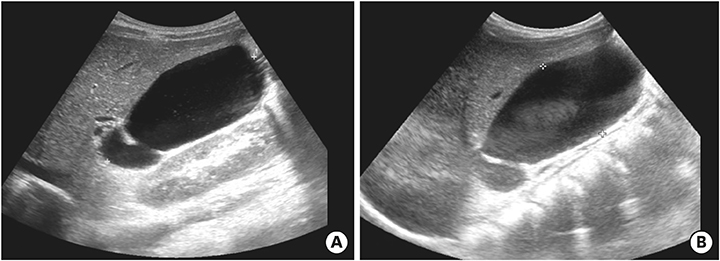

After discharge and 23 days of fever onset, a follow-up abdominal sonography revealed a slower regression of the GB hydrops (Fig. 5A). Echocardiography performed at 81 days after onset of fever revealed complete improvement of both the coronary artery lesion and GB hydrops (Fig. 5B).

Abdominal ultrasonography (A) performed at 23 days after fever onset revealed a slow regression of the gallbladder hydrops (6.7×3.2 cm in size). Echocardiography (B) performed at 81 days after fever onset revealed a complete improvement in gallbladder hydrops and a normal gallbladder.

Fig. 5 Abdominal ultrasonography (A) performed at 23 days after fever onset revealed a slow regression of the gallbladder hydrops (6.7×3.2 cm in size). Echocardiography (B) performed at 81 days after fever onset revealed a complete improvement in gallbladder hydrops and a normal gallbladder.